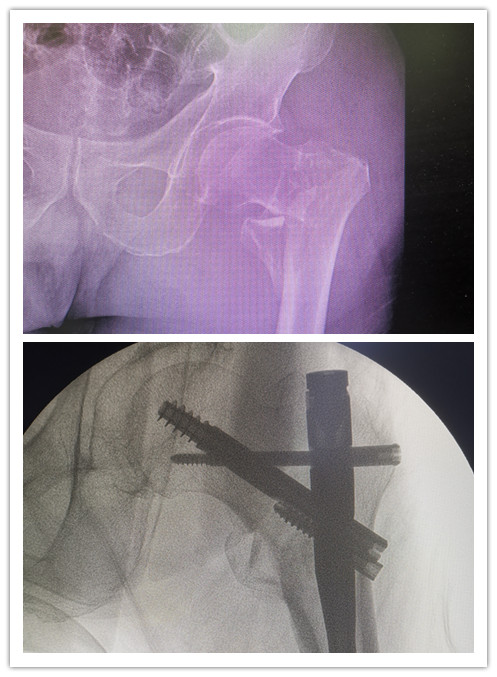

前不久,89歲的廖老因為走路時不小心摔傷左髖部,被緊急送到石化醫(yī)院。X線檢查顯示,廖老的左股骨轉(zhuǎn)子間粉碎性骨折。在完善相關(guān)輔助檢查后,骨科副主任醫(yī)師楊琲、錢立標(biāo)帶領(lǐng)團(tuán)隊認(rèn)真研究患者影像資料,考慮其基礎(chǔ)疾病較多,有高血壓、糖尿病以及重度骨質(zhì)疏松癥病史,再結(jié)合年齡、病情和康復(fù)鍛煉需要,召集多學(xué)科綜合會診評估風(fēng)險。經(jīng)與患者和家屬積極溝通,最終決定運用股骨髓內(nèi)釘系統(tǒng)PFBN,為廖老行股骨轉(zhuǎn)子間骨折閉合復(fù)位內(nèi)固定手術(shù)。

手術(shù)當(dāng)日,在麻醉科的協(xié)助下,骨科團(tuán)隊經(jīng)透視成功將廖老的左髖部牽引復(fù)位,用4個小切口順利置入PFBN固定,不到40分鐘就成功完成手術(shù)。